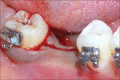

The interdisciplinary collaboration of periodontics and orthodontics has allowed teeth to be moved 2-3 times faster, reducing the time required for traditional orthodontic therapy considerably. Periodontally accelerated osteogenic orthodontics (PAOO), also known as Wilckodontics, is a combination of a selective decortication facilitated orthodontics and alveolar augmentation. With this technique, there is no dependence on the pre-existing alveolar volume. This case report describes the treatment of permanent mandibular molar protraction in a 14-year-old patient undergoing orthodontic therapy using PAOO with piezosurgery.